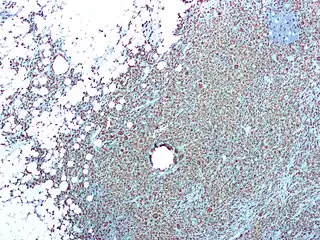

Pielonefritis

La pielonefritis o infección urinaria alta es una infección del riñón que involucra el parénquima renal, la pelvis renal y los cálices renales. Normalmente, los microorganismos que la producen ascienden desde la vejiga hasta el parénquima. Se caracteriza por dolor al orinar, fiebre, escalofríos, dolor en el flanco y la zona lumbar, náuseas y vómitos.[1][2]